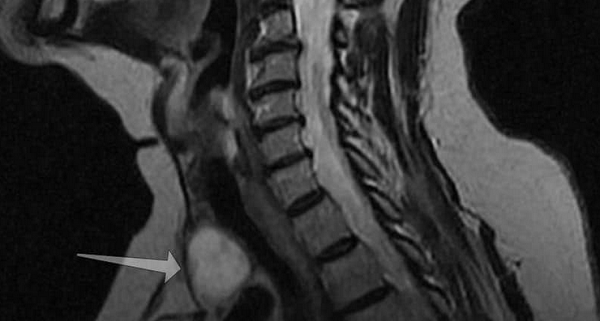

Новообразование (указано стрелкой) на МРТ щитовидной железы